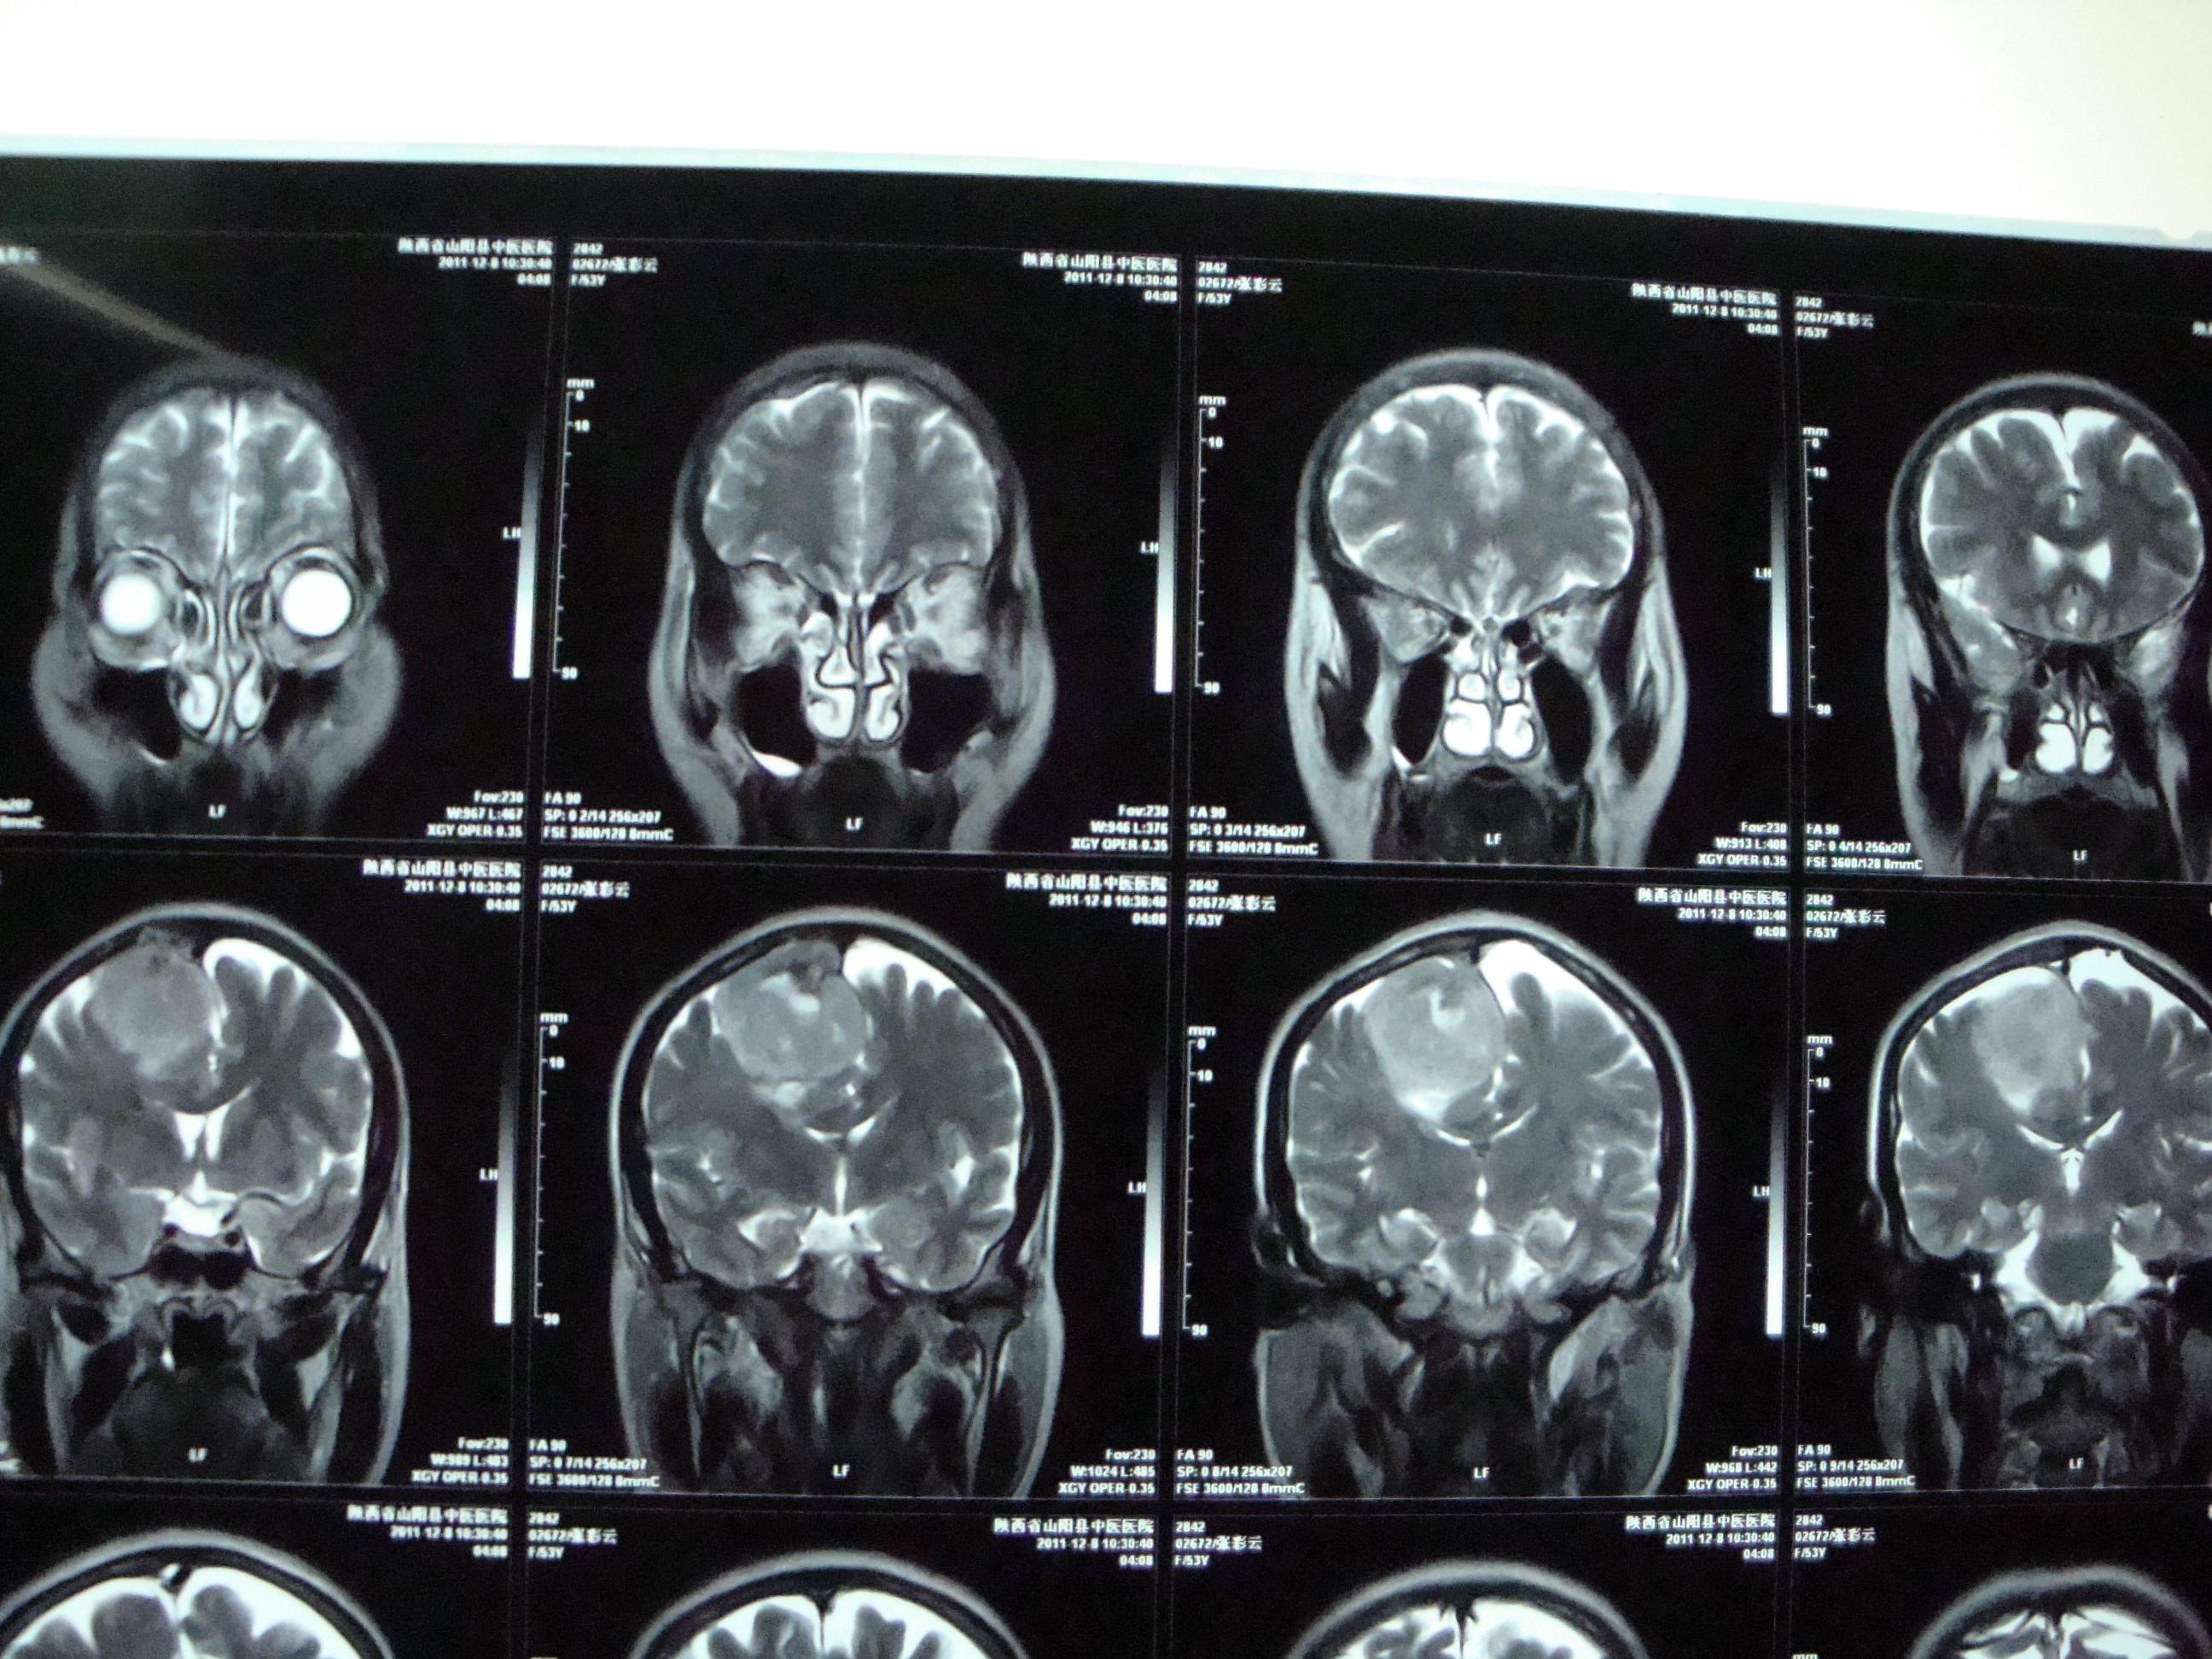

右侧额顶叶占位脑膜瘤可能

图片尺寸3264x2448